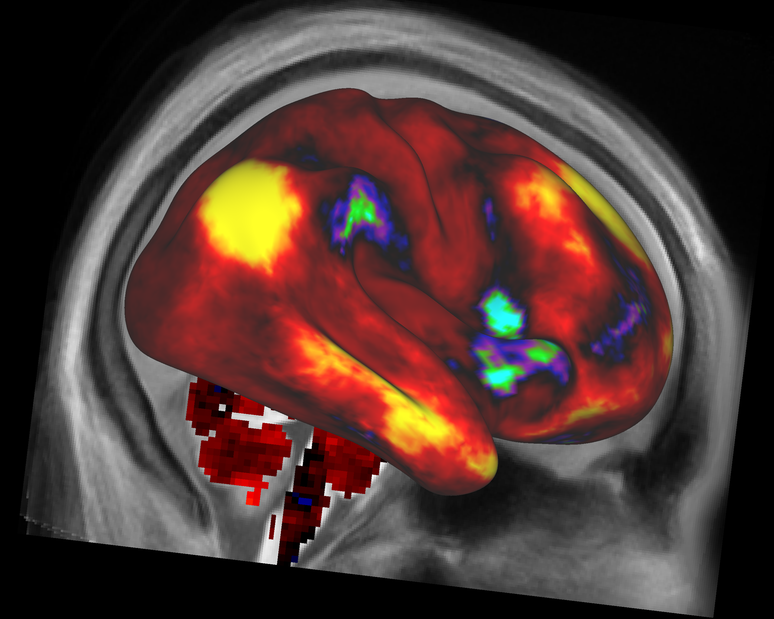

<p>Na imagem, um mapa de conectividade funcional média no córtex cerebral. Regiões em amarelo são funcionalmente ligadas a uma semente localizada no lobo parietal do hemisfério direito, enquanto que as regiões em vermelho e laranja são fracamente ligadas ou não apresentam ligação</p>

Na imagem, um mapa de conectividade funcional média no córtex cerebral. Regiões em amarelo são funcionalmente ligadas a uma semente localizada no lobo parietal do hemisfério direito, enquanto que as regiões em vermelho e laranja são fracamente ligadas ou não apresentam ligação

Foto: Human Connectome Project / Divulgação